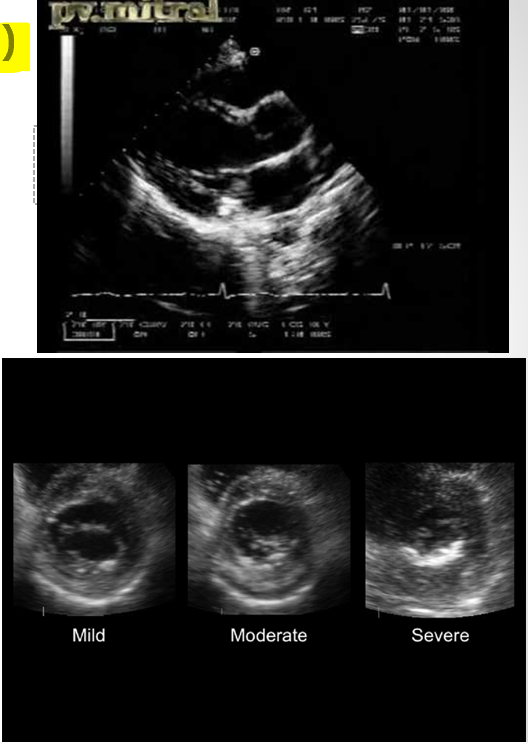

what is the range for mild, moderate, and severe stenosis with regarding mean gradients of mitral valve?**

mild : <5mmHg

moderate : 5-10mmHg

severe : >10mmHg